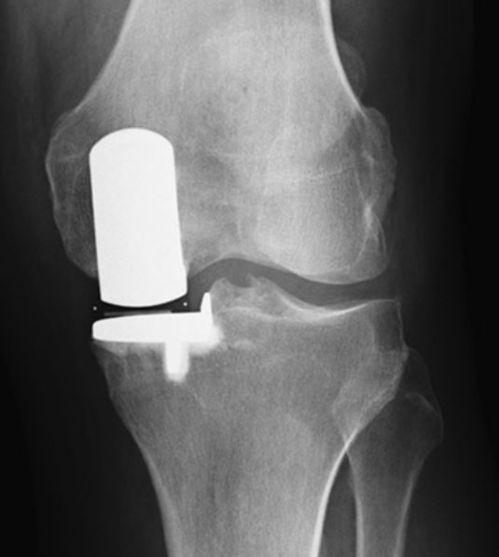

手术过程中,医生会根据你的病情选择合适的手术方式。如果是关节镜手术,他们会将镜子插入你的膝盖,然后进行操作。如果是开放式手术,医生会在你的膝盖处切开一个切口,然后进行修复。

还有一位名叫张先生的患者,因为膝盖骨折,进行了开放式手术。虽然恢复过程比较痛苦,但他依然坚持下来,最终成功康复。